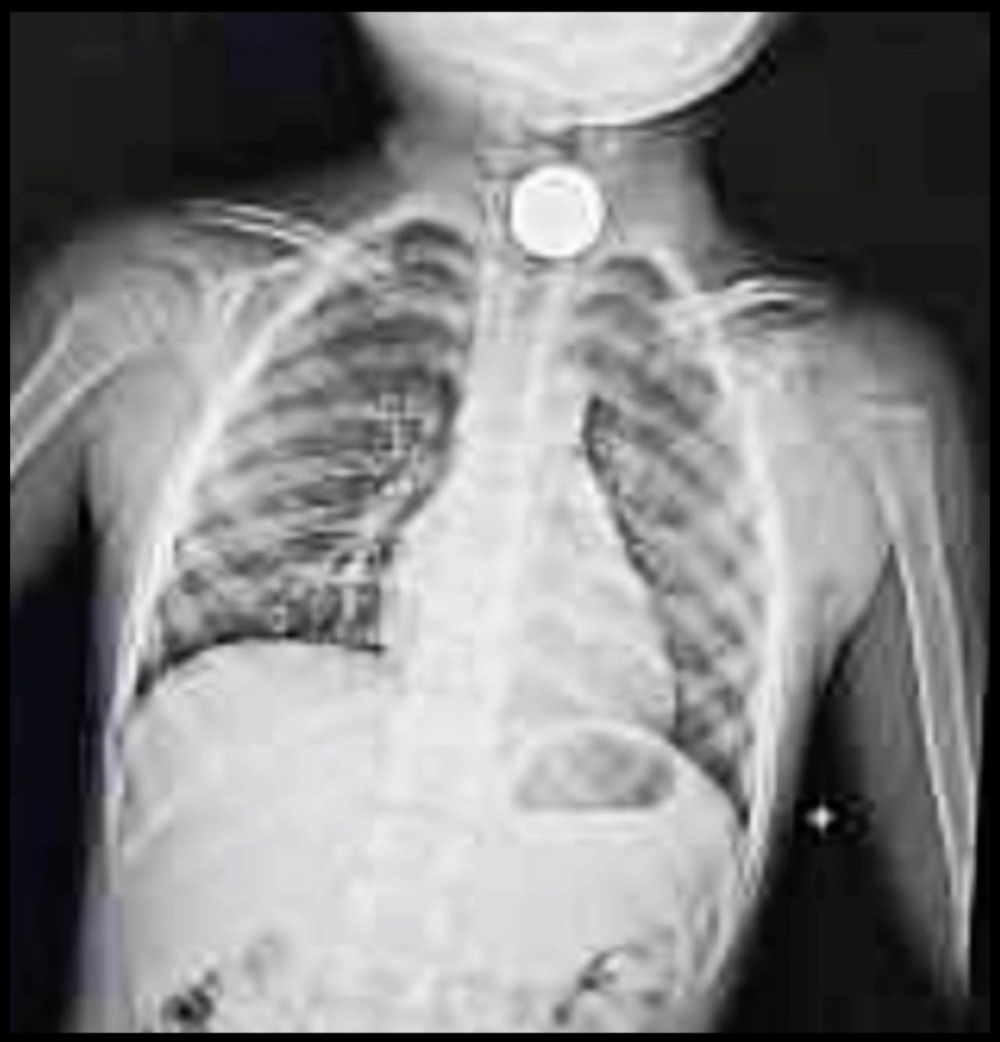

他續指,抵達醫院接受檢查時,兒子可能過於緊張而吐了一地,當時他心想:「也沒有吐出東西啊?應該就沒事吧!」直到X光結果出來,他才看見真的有硬幣卡在兒子喉嚨,醫生即刻建議他們轉診大醫院接受治療。

Photo from 翻攝自羅文裕FB